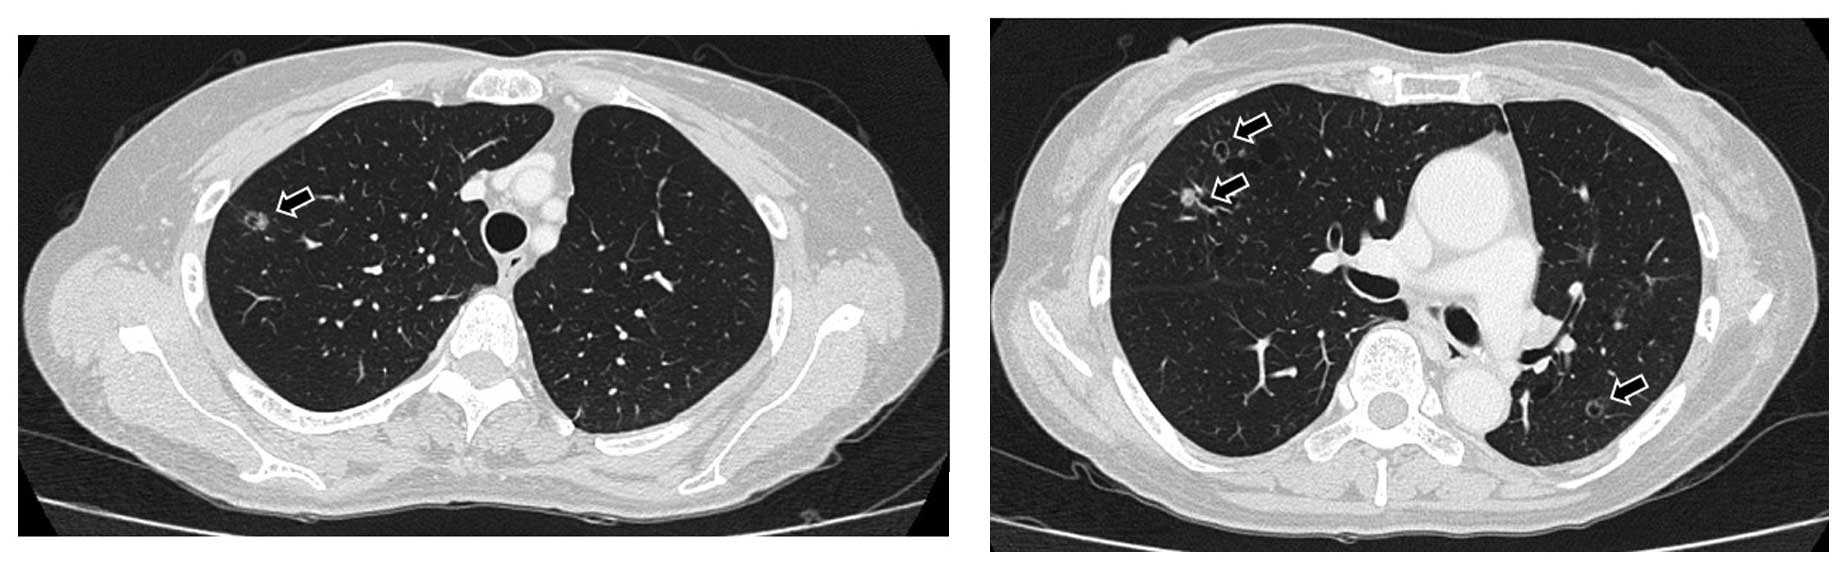

Figure 2.

Chest computed tomography (CT) scan 6 months after the initiation of chemotherapy, showing small cavitary metastases sized ≤10 mm in both lungs (arrows). CT imaging slice at the level of the sub-carina (right panel), and at the level of the upper part of the trachea (left panel).

Figure 3.

Chest computed tomography (CT) scan on day 28 of pemetrexed-containing chemotherapy, showing significant regression of the metastatic cavitary tumors in both lungs, with thinning of the walls (arrows). CT imaging slice at the level of the sub-carina (right panel), and at the level of the upper part of the trachea (left panel).

A 66-year-old woman with no history of smoking presented to Mito Medical Center, University of Tsukuba (Tsukuba, Japan) with a cough and intermittent hemoptysis over the past 8 weeks. Chest radiography and computed tomography (CT) revealed a large cavitary mass in the lower lobe of the left lung. Bronchoscopy revealed a tumor occluding the left lower bronchus, with active bleeding. The patient was initially diagnosed with adenocarcinoma on the basis of the histopathological examination of transbrochial biopsy specimens. Distant metastasis was not detected. The Eastern Cooperative Oncology Group performance status score was 1. To prevent the deterioration of her respiratory condition due to hemoptysis, the patient underwent a lobectomy of the left lower lung and mediastinal lymph node dissection. The resected tumor consisted of adenocarcinomatous as well as squamous cell carcinomatous components, with each comprising ≤10% of the tumor. The final pathological diagnosis was ASCLC (Fig. 1) and the tumor was staged as pT3bN1M1a. The adenocarcinomatous and squamous cell carcinomatous components of the surgically resected tumor were precisely separated by manual microdissection under microscopic observation to avoid contamination of each sample by different components. An EGFR exon 19 deletion was identified in both components. Soon after the surgical resection, the patient received 4 courses of chemotherapy with carboplatin and pemetrexed. Six months after the chemotherapy, the patient developed small cavitary metastases sized ≤10 mm in both lungs. Therefore, treatment with 250 mg of gefitinib therapy once daily was initiated. A chest CT scan revealed regression of the metastatic cavitary tumors bilaterally, which was evaluated as partial response (PR). The patient developed a grade 2 skin rash, according to the 2013 National Cancer Institute Toxicity Criteria (http://ctep.cancer.gov). One year after the initiation of gefitinib therapy, small cavitary metastases sized ≤10 mm were again detected in both lungs (Fig. 2). The patient strongly wished to receive pemetrexed-containing chemotherapy again, due to its mild adverse event profile. Considering the metastases being confined to the lungs and her good general condition, the patient received chemotherapy with carboplatin, pemetrexed and bevacizumab. After receiving 2 cycles of the chemotherapy, she achieved a PR (Fig. 3) and received an additional 2 cycles of the regimen. Subsequently, 15 cycles of maintenance therapy with pemetrexed and bevacizumab were administered. There was no severe hematological or non-hematological toxicity. Treatment with bavacizumab-containing chemotherapy has been continued at the outpatient clinic, without any signs of tumor progression 19 months after the initiation of pemetrexed-containing chemotherapy.